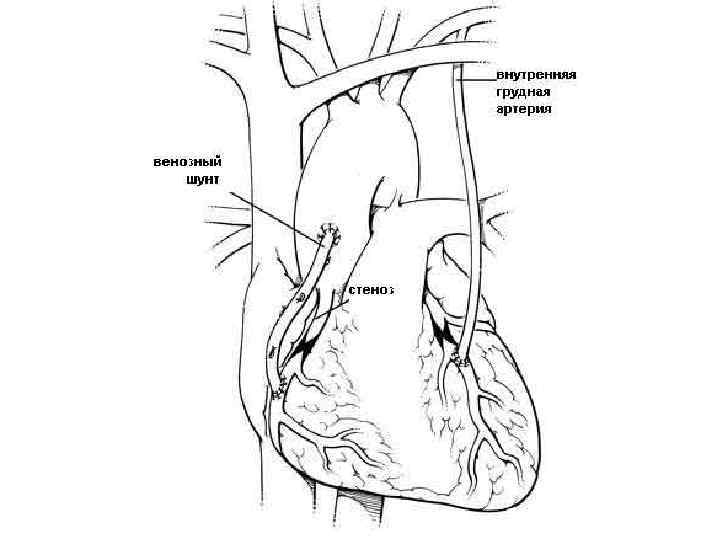

Миокард реваскуляризация әдісі АКШ – зақымдалған тәж артреиясынан айналып өту арқылы, айналма жол жасау Маммокоронарлы шунттау. Бұл кезде ішкі кеуда артреиясын пайдаланып, оны тәждік қанайналымға ауысытырады Аортакоронарлы шунттау. Бұл кезде бос кондуит н/е аутотрансплантантты пайдаланады. Дистальды бөлігін стеноздан төмен тәж артериясымен, ал проксимальды бөлігін аортаның жоғарылаған бөлігімен байланыстырады

Миокард реваскуляризация әдісі АКШ – зақымдалған тәж артреиясынан айналып өту арқылы, айналма жол жасау Маммокоронарлы шунттау. Бұл кезде ішкі кеуда артреиясын пайдаланып, оны тәждік қанайналымға ауысытырады Аортакоронарлы шунттау. Бұл кезде бос кондуит н/е аутотрансплантантты пайдаланады. Дистальды бөлігін стеноздан төмен тәж артериясымен, ал проксимальды бөлігін аортаның жоғарылаған бөлігімен байланыстырады